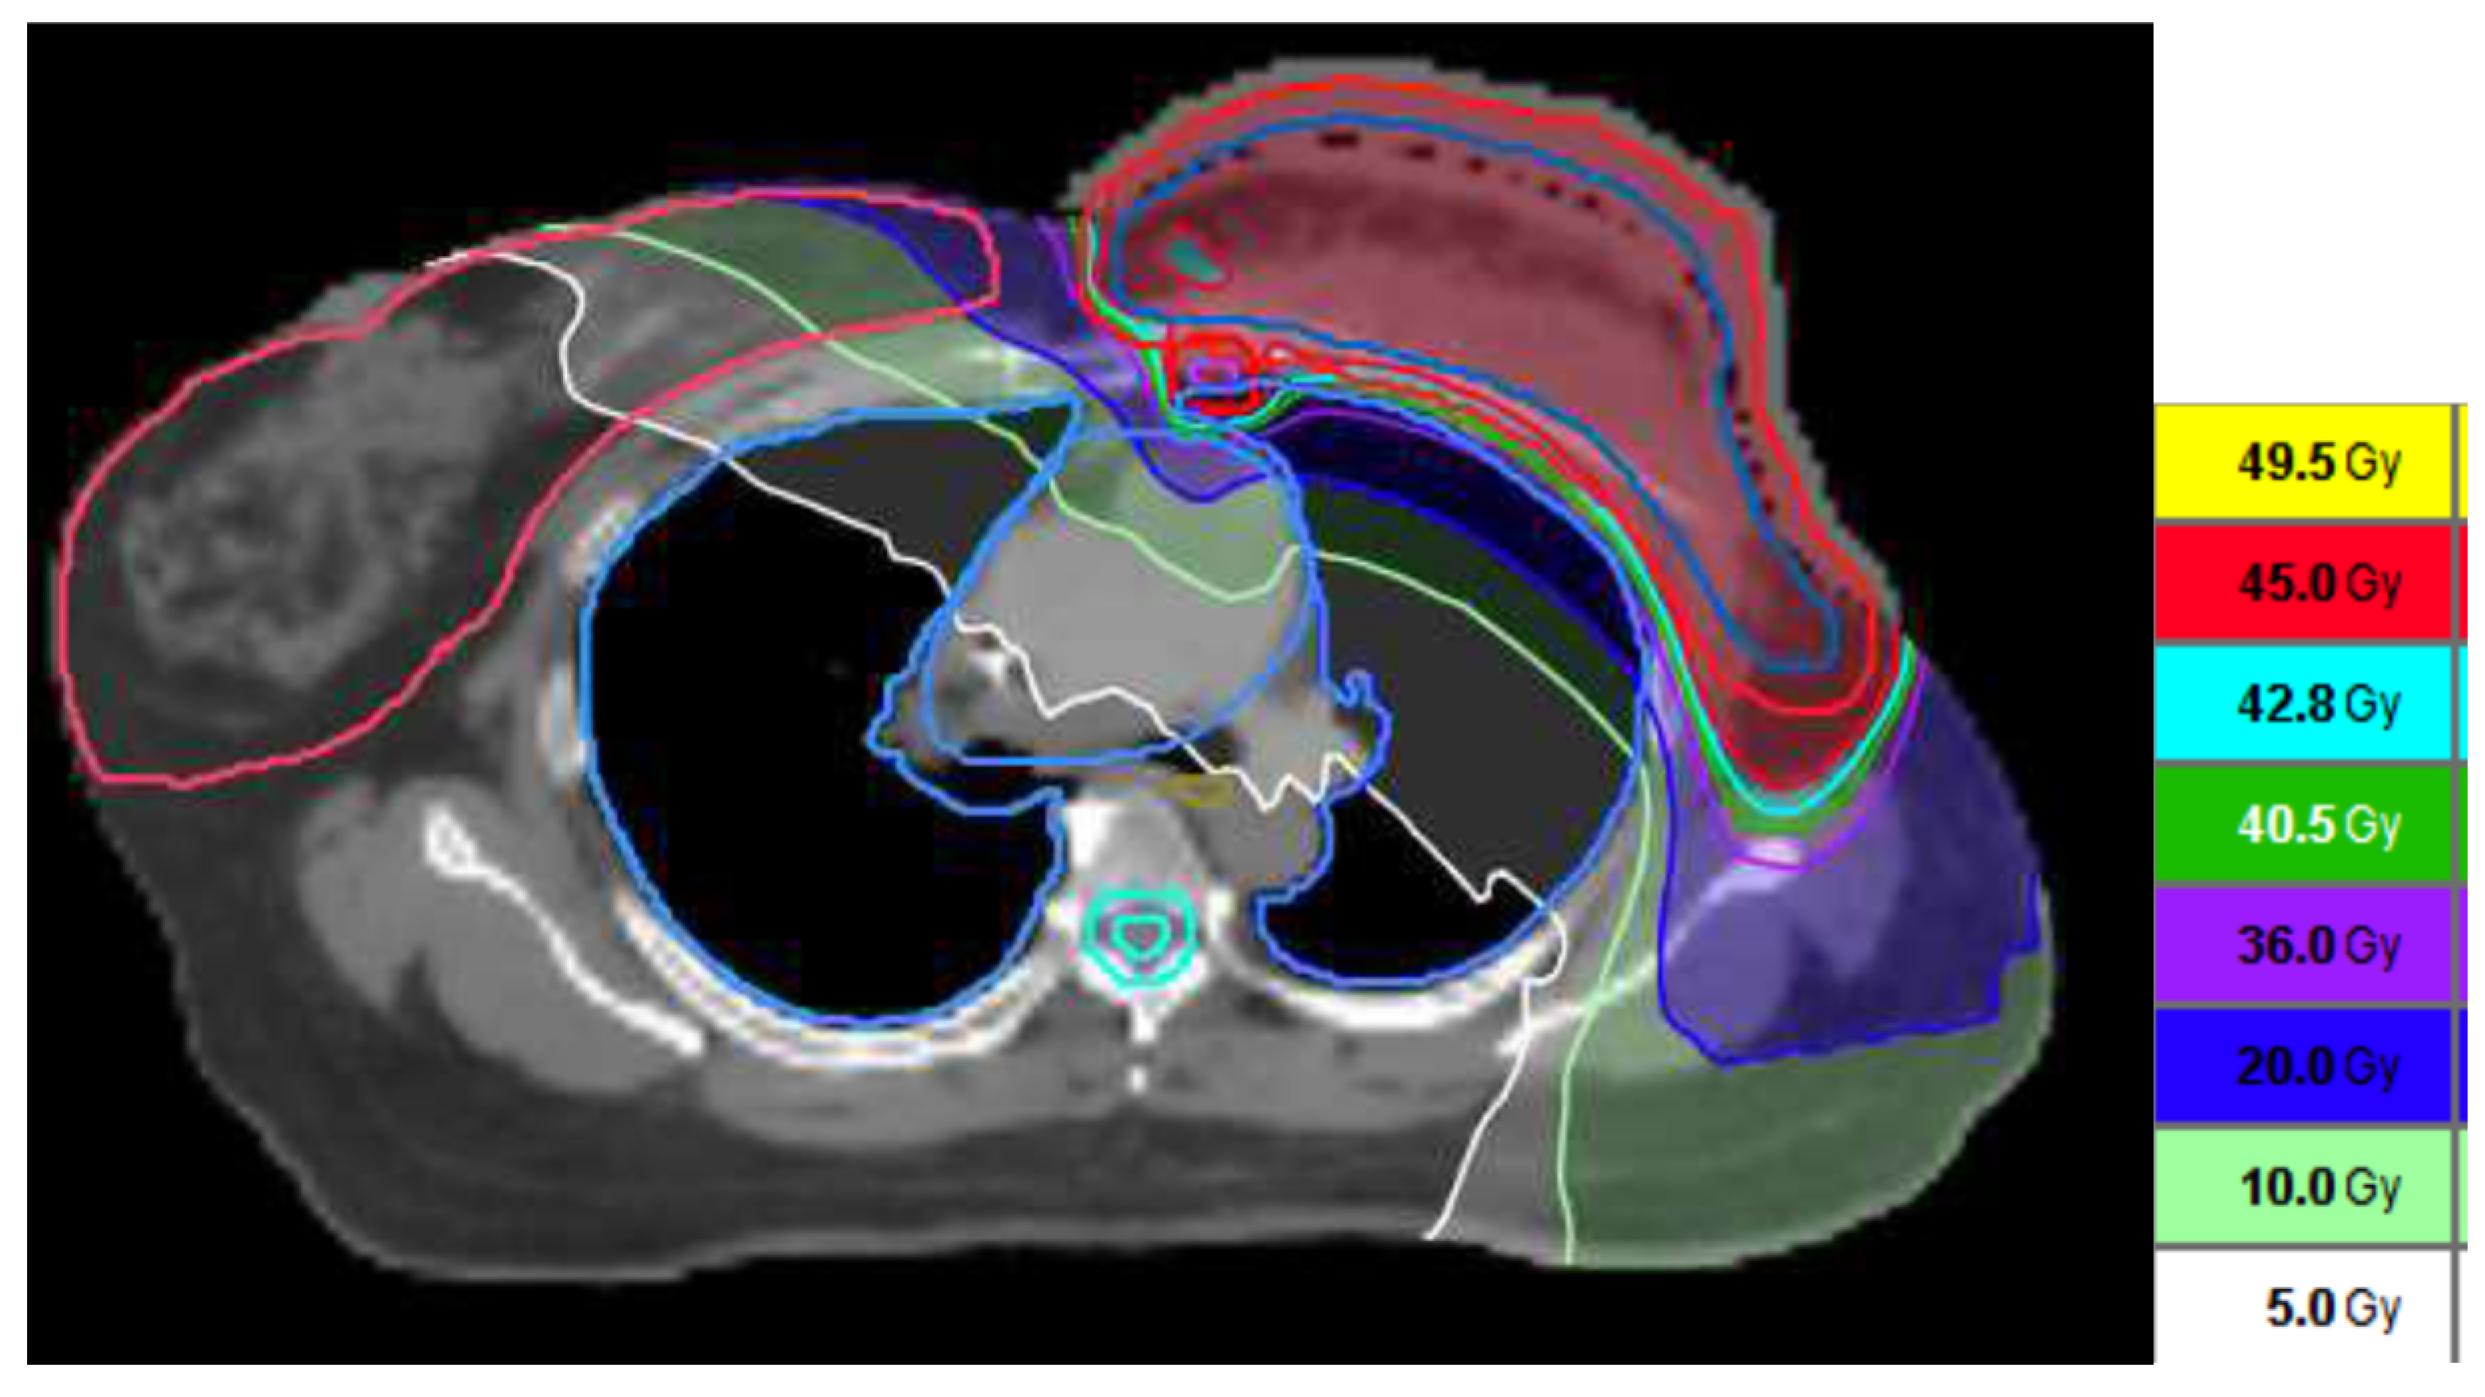

2.2. RT Treatment Plan

2.3. RT Techniques and Dosimetry Evaluation